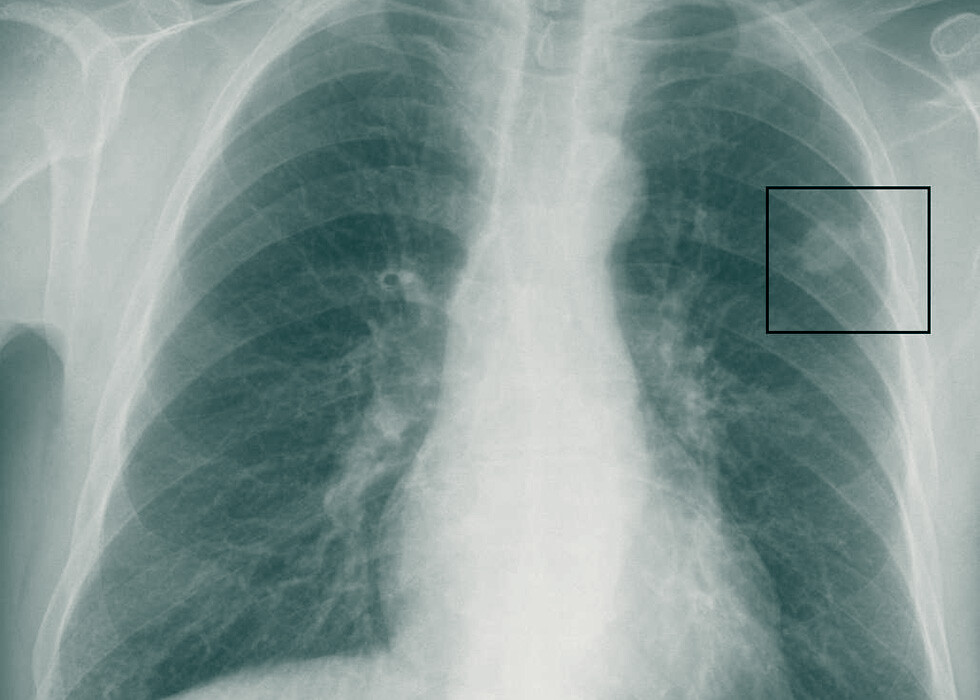

Was zeigt Röntgenbild? Kompetente Interpretation des

Was zeigt Röntgenbild? Kompetente Interpretation des Röntgenbildes der Lunge